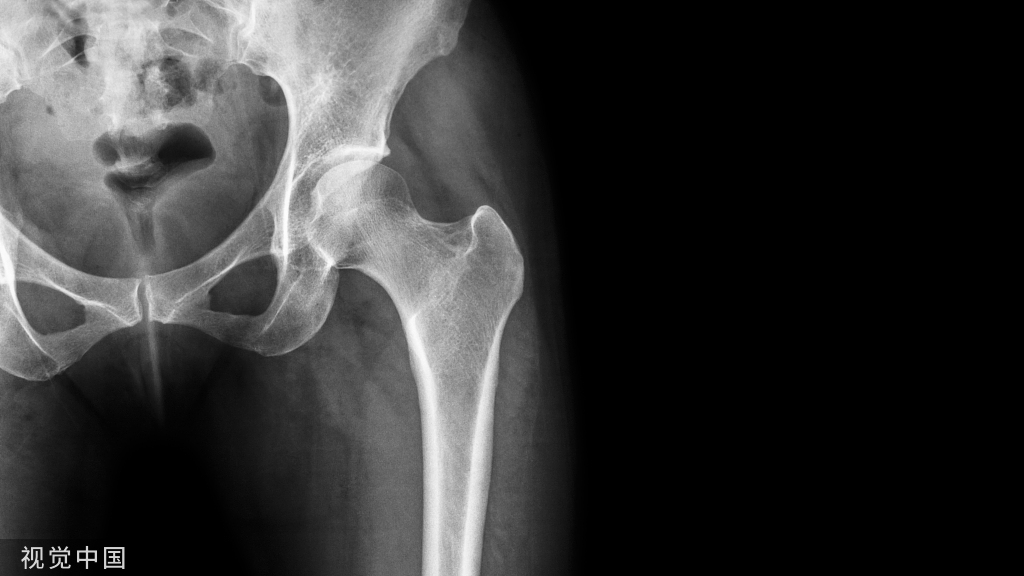

髂骨取骨之切口的操作技巧!

图:沿髂骨冠状面切取全层骨板的方法